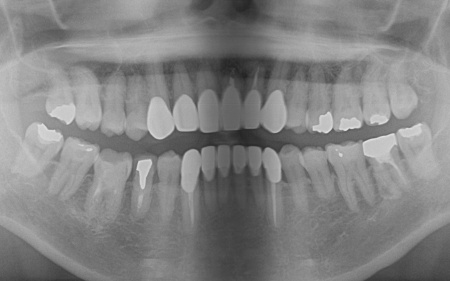

拝見したところ、上下前歯には金属製の土台「メタルコア」を使用した被せ物(クラウン)が装着されており、被せ物と歯茎の境目付近が黒くなっていました。

また、保険適用の白い詰め物(コンポジットレジン)が充填されている部分には変色が見られます。ご自身の歯、被せ物、コンポジットレジン、それぞれの色調が異なっていることで審美性に影響が出ているため、上下前歯(合計12本)の被せ物と詰め物を新しくする必要があると診断しました。

また、左上前歯2本と左右下前歯2本は、細菌感染した神経を取り除いてから薬を詰める「根管治療」が施されていましたが、薬が歯根の先までしっかり詰められていなかったため、「再根管治療」が必要であることも併せてお伝えしています。